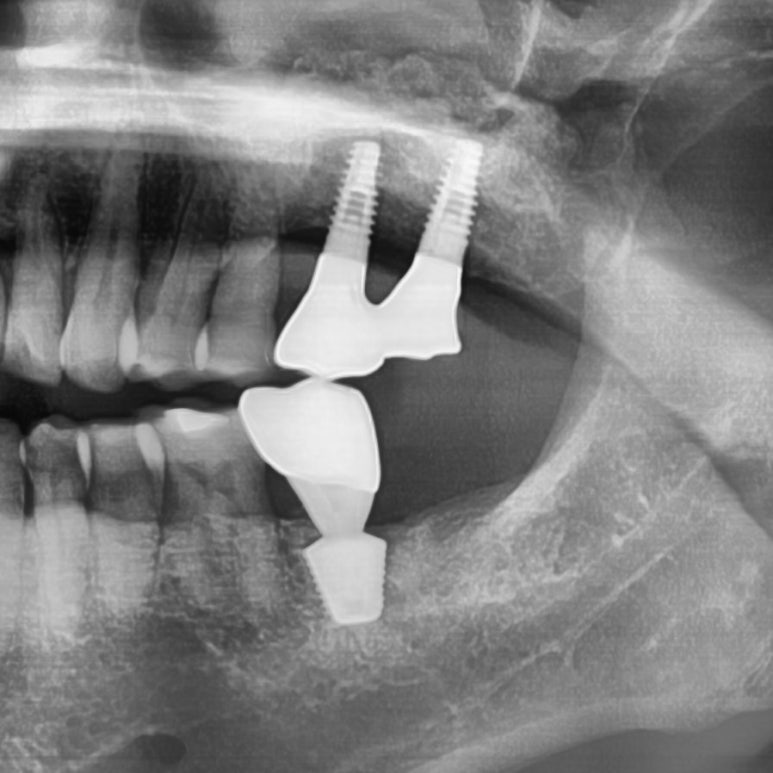

![[서울시청역치과] 다른 치과에서 오래전에 한 임플란트가 흔들려요 →재수술 케이스 관련 이미지 6](https://pub-9f2bb3498faf4d1d8714b41df24753e3.r2.dev/content/clinics/archive/rseeanjxfu/naver_blog/yonseiyegam/assets/by_hash/ea84db90f4b4850aa69afcafff7f723e6ab5ab76a91014b226204aea64acdc6b.jpg)

연결된 2개 인플란트 중

앞쪽 임플란트는 많이 흔들리는 상태였고 뒤쪽 임플란트도 반만 주변 뼈가 잡고있어 오래 못쓸거 같아

같이 빼기로 하였습니다.

또한 바로 앞의 치아도 많이 흔들려서 나중에 또 고생하느니 같이 발치하기로 하였습니다.